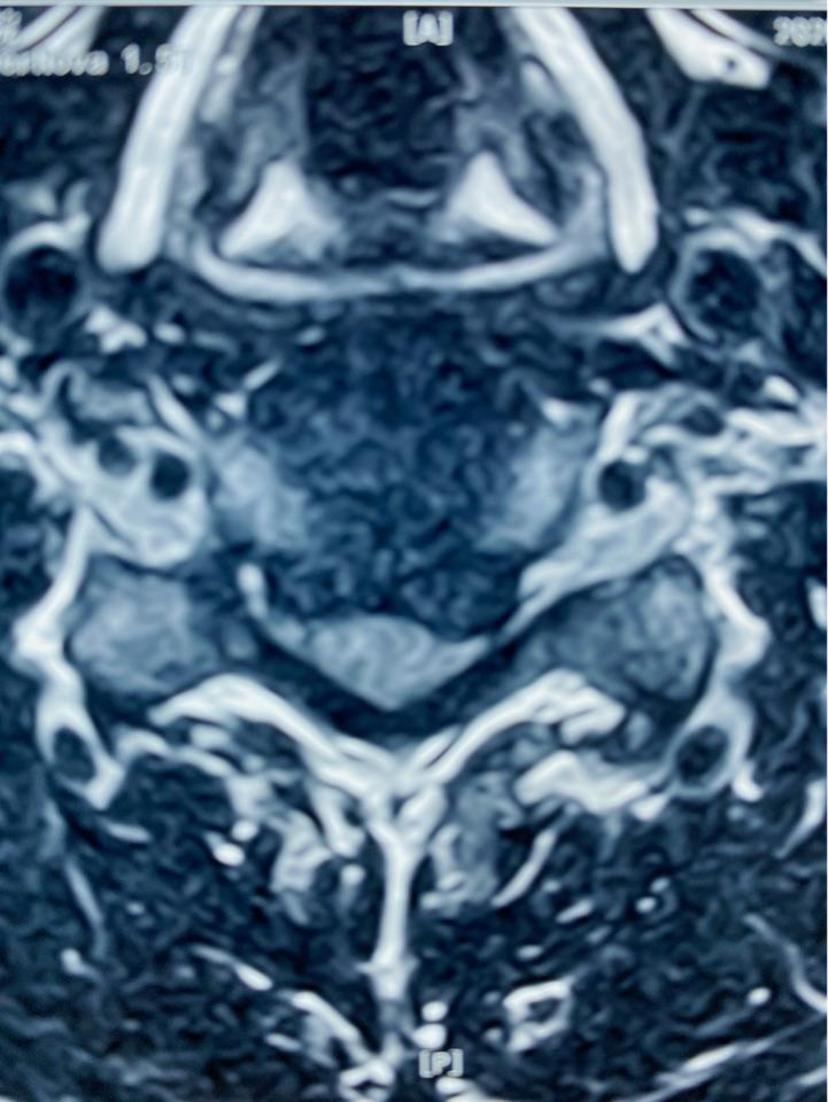

四肢麻木无力,走路不稳,平时需要家人搀扶、拄拐杖走路,行颈前路微创手术,术程不到1小时,切口2cm,术中出血不到10ml,术后第二天下地自行走路,第三天自己弃拐带小跑出院!颈5-6椎间盘突出继发椎管狭窄,脊髓神经严重受压左侧神经严重受压颈椎反弓术中完整取出压迫脊髓神经的椎间盘术后片子位置良好,颈椎反弓完全纠正术后第三天四肢力量明显恢复,麻木感消失,自己甩掉拐杖带小跑出院